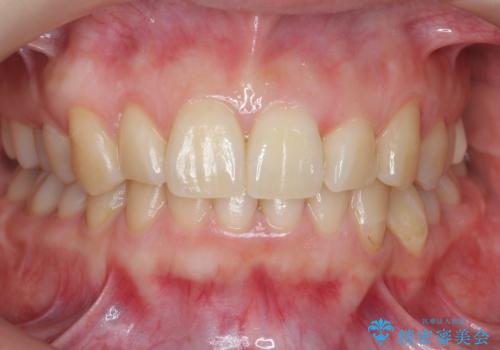

結果それなりに並んで問題ない状況にはなったと思います。

奥歯を後ろに送るために、矯正用ミニスクリューを使用しました。

また、下顎の前歯から奥歯にかけて歯を少し削るIPRを行なっています。